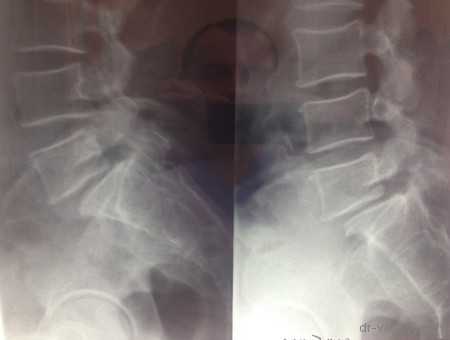

МРТ до операции

Рентген до операции